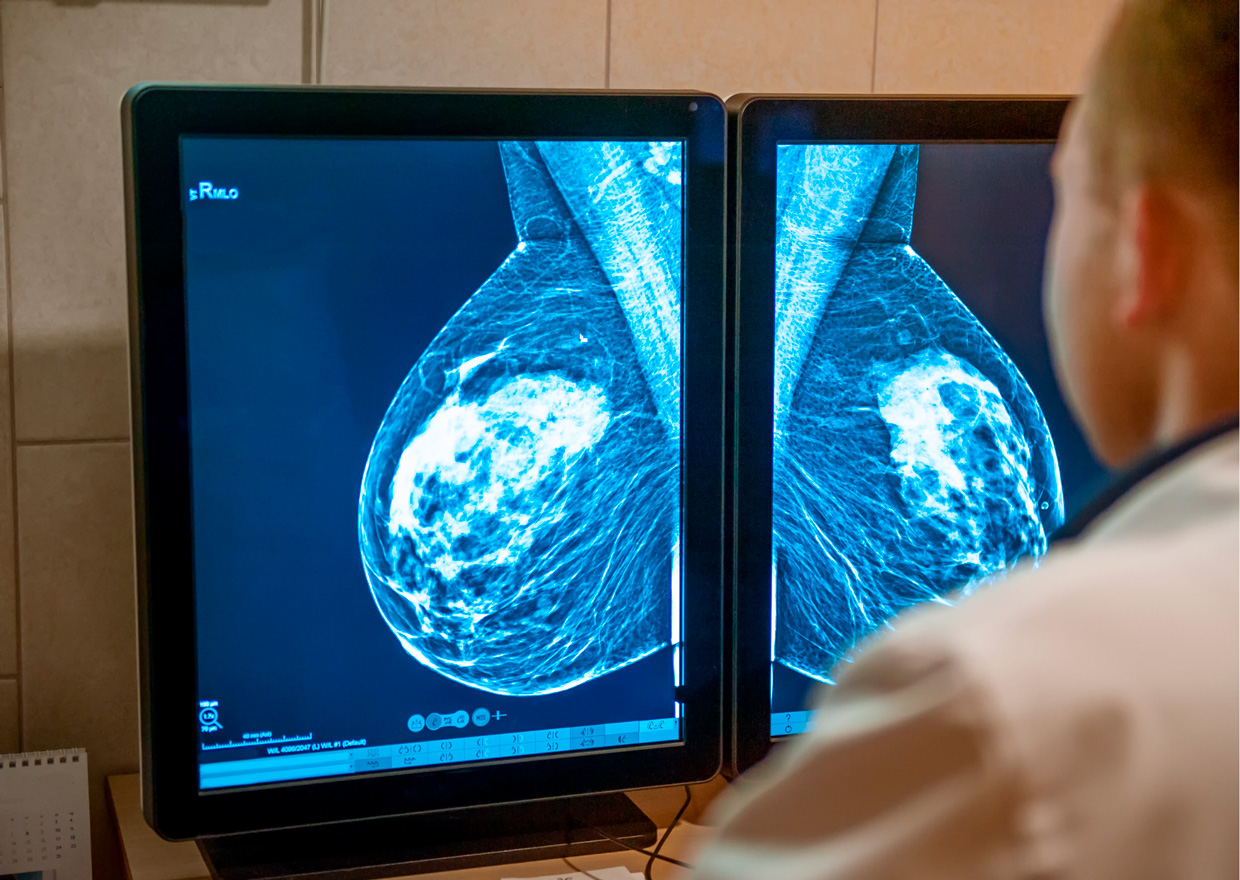

Los médicos utilizan distintos tipos de pruebas para detectar o diagnosticar el cáncer de mama. En la mayor parte de los tipos de cáncer, una biopsia es la única manera segura para que el médico determine si un área específica del cuerpo tiene cáncer.

El diagnóstico del cáncer de mama triple negativo se da una vez que éste se ha detectado mediante estudios por imágenes y biopsia, y tras analizar las células cancerosas se determina si tienen ciertas características. Si las células no tienen receptores de estrógeno o progesterona (ER o PR), y tampoco producen suficiente proteína HER2, se considera que el cáncer de mama es triple negativo.

Ante esta realidad, la Sociedad Americana Contra El Cáncer recomienda para la detección del cáncer de seno, que las mujeres con un riesgo promedio y alto se sometan a un mamograma cada año, por lo general a partir de los 30 años.